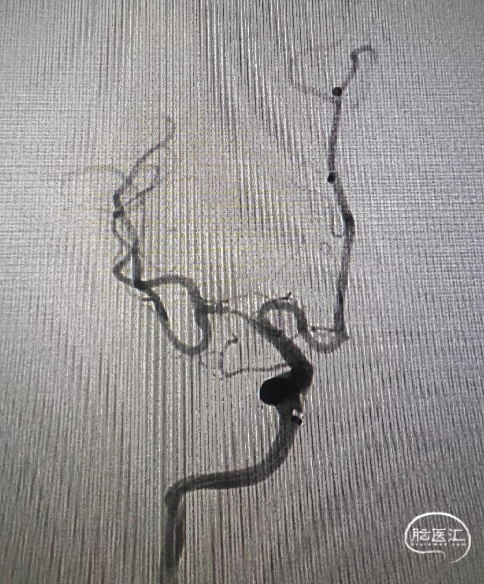

术中证实右侧大脑中动脉M1中段重度狭窄。

使用21系列 Fastunnel®输送型球囊扩张导管 2.0*15mm充分预扩后造影。

使用“零交换”技术沿21系列 Fastunnel®输送型球囊扩张导管 2.0*15mm上行自膨式闭环支架 3.0*21mm,到位后顺利释放。